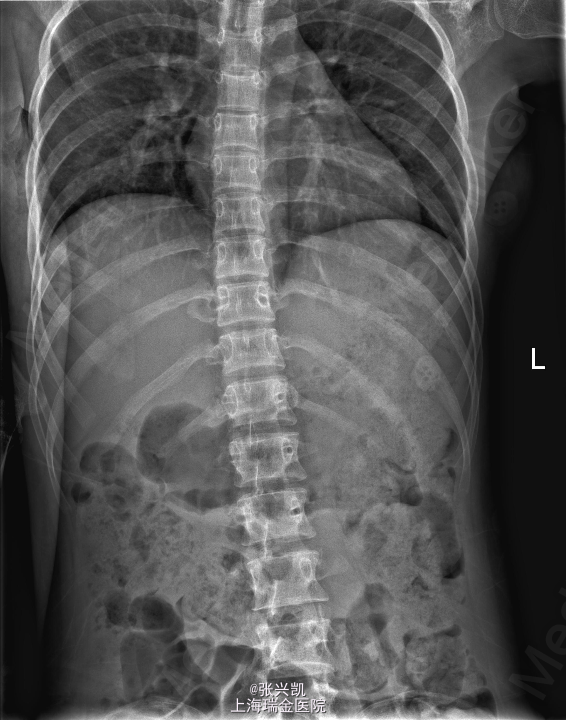

检查:腰背部叩痛,压痛明显,脊柱无侧弯,双下肢肌力及感觉正常,膝腱反射等存在,巴氏征(-)。 辅助检查:X线平片示:T11,L椎体骨折 头颅CT及肋骨CT示:T11椎体,左侧横突及椎弓,及L1椎体骨折 MR:T11,L1椎体新鲜骨折

诊断:多发胸腰椎骨折(T11,L1) 处理:胸腰椎骨折经皮椎弓根钉复位内固定术,一年后骨折愈合良好,行内固定装置取出术

随访:术后三月复诊,内固定装置位置良好,患者腰背痛症状缓解,一年后骨折愈合,行内固定装置取出。术后患者腰部活动良好 讨论:术后应积极锻炼腰背部肌肉,防止萎缩。